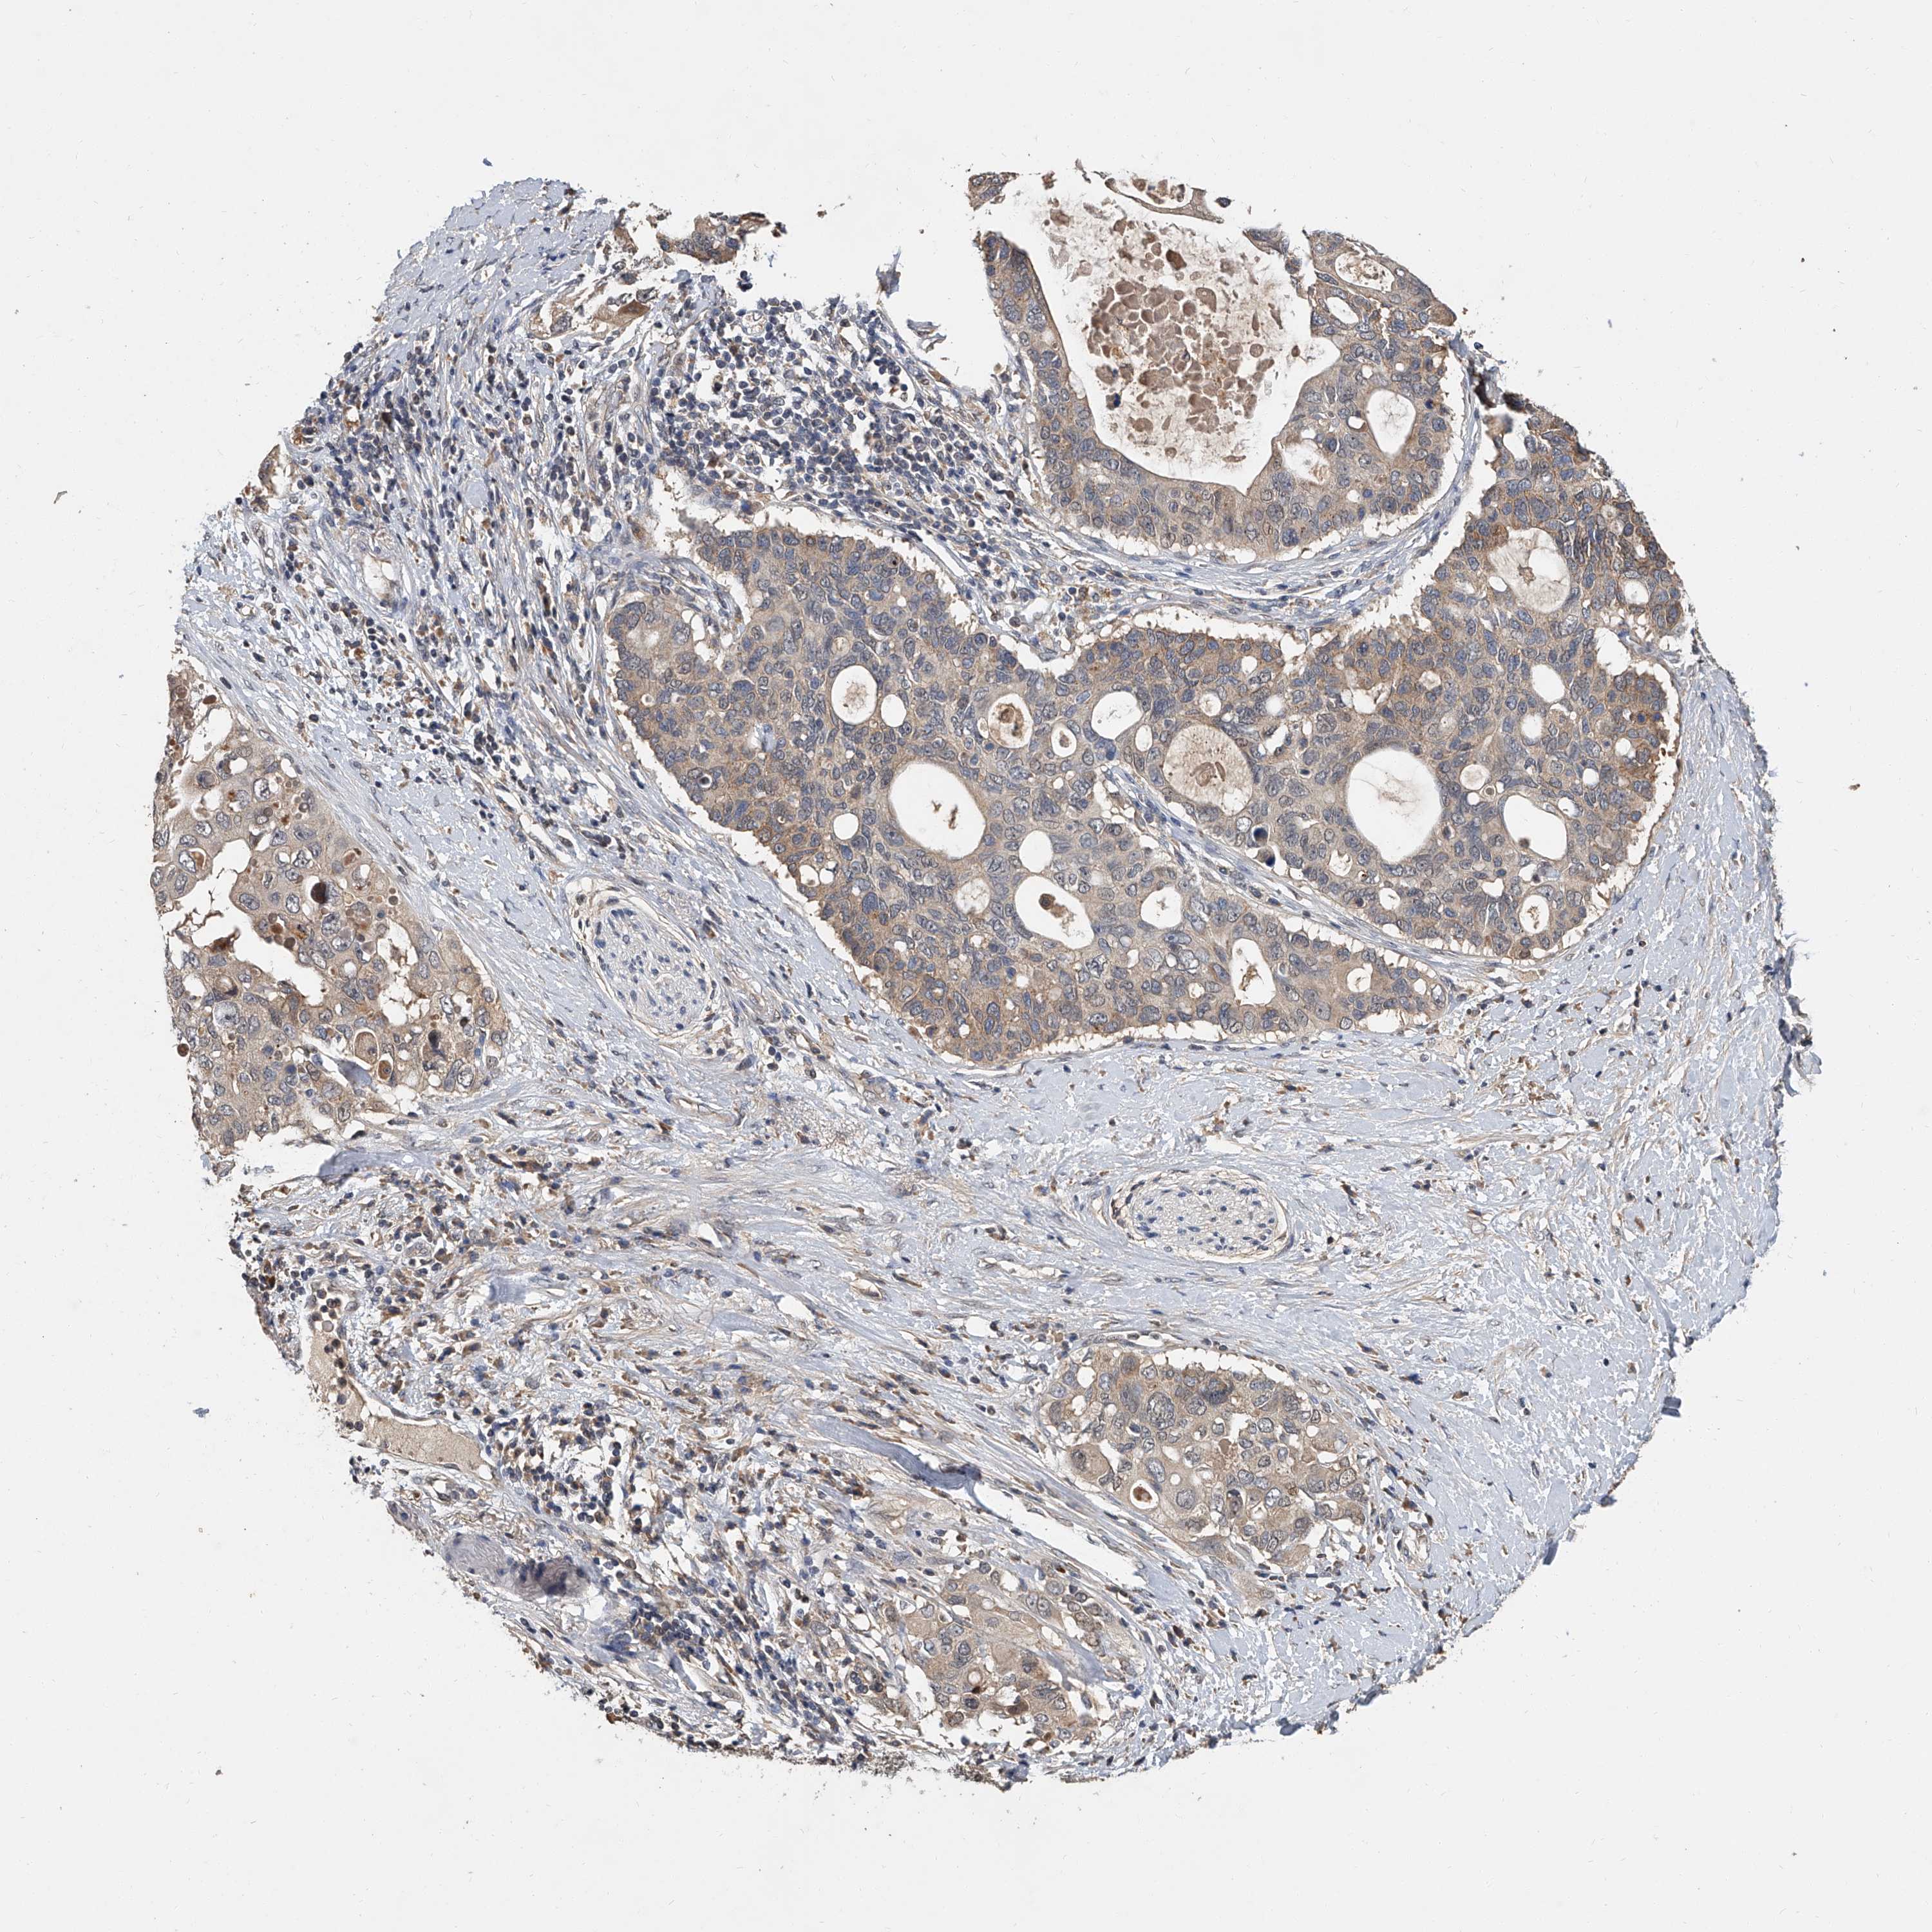

PANCREATIC CANCER - Protein expressioni

A mouse-over function shows sample information and annotation data. Click on an image to view it in a full screen mode. Samples can be filtered based on level of antibody staining by selecting one or several of the following categories: high, medium, low and not detected. The assay and annotation is described here.

Note that samples used for immunohistochemistry by the Human Protein Atlas do not correspond to samples in the TCGA dataset.

Antibody stainingi

Antibody staining in the annotated cell types in the current human tissue is reported as not detected, low, medium, or high, based on conventional immunohistochemistry profiling in selected tissues. This score is based on the combination of the staining intensity and fraction of stained cells.

Each image is clickable and will lead to virtual microscopy that enables deeper exploration of all samples and also displays staining intensity scores, fraction scores and subcellular localization as well as patient and tissue information for each sample.

Antibody HPA030636

Antibody CAB025481

Staining

High

Medium

Low

Not detected

Intensity

Strong

Moderate

Weak

Negative

Quantity

>75%

75%-25%

<25%

None

Location

Nuclear

Cytoplasmic/membranous

Cytoplasmic/membranous,nuclear

Adenocarcinoma, NOS